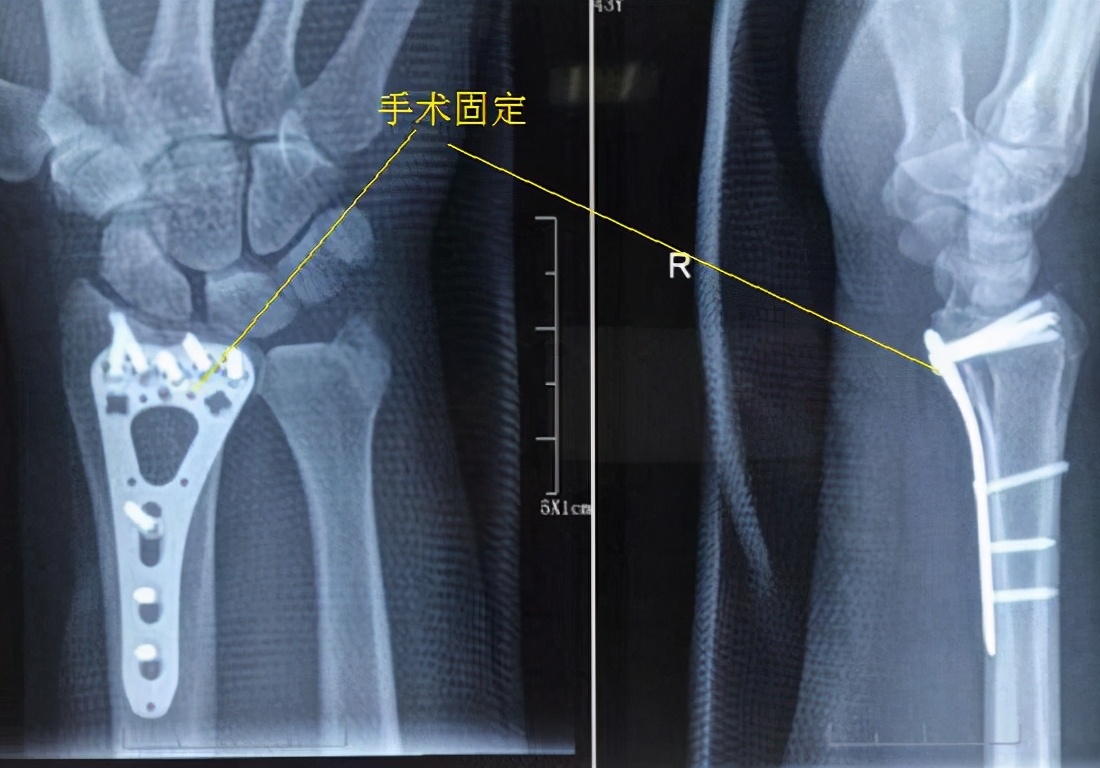

0-6周 1、将首要目标确定为防止肿胀、僵硬。2、稳定型的、非手术治疗的骨折,起初应使用长臂方糖夹式夹板固定肘、腕关节,进行积极的肩关节和手指关节活动练习,在3-4周后当骨折达到一定愈合度时,则要更换只固定腕关节的短臂夹板,并同时进行肘关节的活动练习。如果是牢靠的手术内固定,术后即可开始肩关节和手指关节的活动练习,在拆线后同时进行肘关节的活动练习,并允许腕关节活动(仍要使用短臂夹板在夜间和其他时间对肘关节进行必要固定)。3、尝试进行功能性活动,例如,尝试拿比较轻的物品,抓握东西等。对于稳定的内固定、稳定型骨折、或者骨折愈合到一定程度时,可进行穿衣、吃饭、写字、上厕所等日常活动。4、如果是稳定的内固定,在拆线后就可尝试进行前臂旋前和旋后动作;对于非手术治疗而言,稳定型骨折、或达到一定愈合度的骨折,应尽早实施前臂旋前和旋后练习。5、手术治疗者,采用按摩、硅胶贴等方式处理瘢痕,避免切口区的粘连和挛缩。